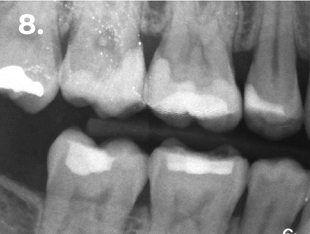

Fig. 2 Radiografia bitewing iniziale

Fig. 8 Radiografia bitewing finale

Esame clinico e radiografico:

• Restauro composito occluso-mesiale

• Carie distale profonda

Diagnosi: Pulpite reversibile

Nell’immagine clinica e radiografica finale si osservano corretti profili anatomici, con adeguata convessità e punti di contatto funzionali.